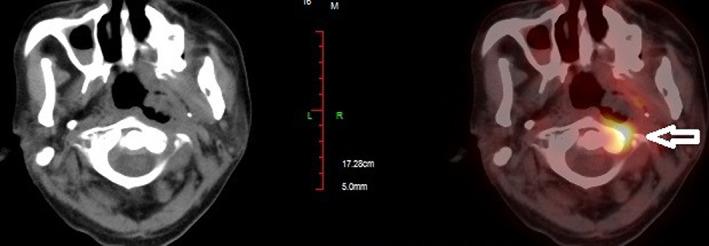

A 42-year-old man had a history of recurrent NPC that was treated with 2 cycles of chemoradiotherapies from 2017 to 2019. Five months after the second round of chemoradiotherapy, an episode of massive nasal bleeding occurred. As positron emission tomography (PET) scan revealed tumor recurrence in the left wall of nasopharynx, superselective embolization and subsequent intra-arterial infusion (IA, 4 times of cisplatin 60 mg + fluorouracil 1.0 g) were performed to stop bleeding and achieve tumor control. To date, the disease-free survival time has been over 1 year. No tumor recurrence or rebleeding is found except for alopecia on the left side.